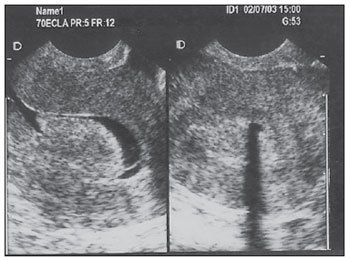

Diagnóstico: nódulo hipoecoico a USG

USG-TV: sugere